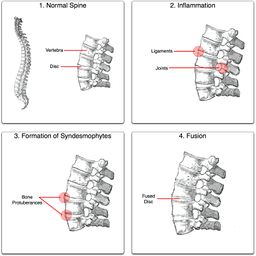

التهاب الفقار المقسط أو اللاصق Ankylosing spondylitis باليونانيةankylos, stiff; spondylos, vertebrae), تسمى قديماًBekhterev's disease, Bekhterev syndrome, و Marie-Strümpell disease هو نوع من التهاب المفصل في العمود الفقري. وهو يسبب تورماً بين الفقرات، والفقرات هي الأجزاء الأسطوانية التي تكون العمود الفقري، كما يسبب تورماً في المفاصل بين العمود الفقري والحوض. إن التهاب الفقار المقسط أو اللاصق هو أحد أمراض المناعة الذاتية. إن الجهاز المناعي المسؤول عن حماية الجسم من العدوى يقوم بمهاجمة أنسجة الجسم نفسها في حالة أمراض المناعة الذاتية. ويكون التهاب الفقار اللاصق أكثر انتشاراً وخطورة عند الرجال. وكثيراً ما يكون مرضاً ينتقل عن طريق الوراثة.[1]

ومن أعراضه المبكرة ألم الظهر والتيبس. وهي تبدأ غالباً في مرحلة المراهقة المتأخرة أو أوائل البلوغ. ومع مرور الوقت يمكن لالتهاب الفقار اللاصق أن يؤدي إلى التحام الفقرات مما يقيد حركتها. يمكن أن تتفاقم الأعراض كما يمكن أن تتراجع أو تختفي تماماً. إن هذا المرض غير قابل للشفاء، لكن الأدوية يمكن أن تهدئ الألم والتورم والأعراض الأخرى. ويمكن أن تكون التمارين الرياضية مفيدة أيضاً.

يبدأ التهاب الفقار المقسط في صغار البالغين بألم مبهم في أسفل الظهر، ويبوسة مديدة تالية للراحة تتحسن جزئياً بالحركة والتمارين الرياضية. ينتشر الألم إلى الاليتين والقسم الخلقي من الساقين. كما يحدث ألم في القفص الصدري بإصابة المفاصل الغضروفية المركزية فيه، وقد يكون لهذا الألم صفات جنبية، ويظهر الألم أيضاً في مفاصل قبضة القص Manubriosternal والمفاصل القصية الترقوية. إن التهاب ارتكازات الأربطة والأوتار عرض بارز وقد يكون العرض الأول. وينجم الألم عن التهاب الأصابع Dactylitis ' أو وتر أشيل، أو اللفافة الأخمصية، أو عرف الحرقفة iac أ I Crest. تكون الإصابة المفصلية بشكل الام مفصلية، أو التهاب مفاصل عديد، يصيب المفاصل الزليلة الدانية وبشكل غير متناظر كالكتفين والمرفقين والركبتين ونادرا المفاصل الصغيرة القاصية. وتترافق هذه الإصابة بيبوسة صباحية مديدة وأحياناً بتورم الا أنه من غير الشائع حدوث إصابة مفصلية تاكلية شديدة.

يحدث التهاب العنبية الأمامي في حوالي ربع المرضى، ويتظاهر بألم واحمرار وخوف من الضياء، وتكون هذه الإصابة نوبية، وحيدة أو ثنائية الجانب. يبدي الفحص السريري نقصاً في حركية العمود الفقري، مع فقد تام أو جزئي للقعس القطني الفيزبولوجي، وزيادة في الحدب الظهري. أما المظاهر المتأخرة فتشمل تحدد حركة جدار الصدر في الشهيق العميق (أقل من 2.5 سم) مع انحناء تدريجي، وثبات العمود الفقري والرأس في وضعية العطف. ويمشى المريض جاراً قدميه Shuffling Gait مع تفاوت شدة إصابة المفاصل المحيطة.[2]